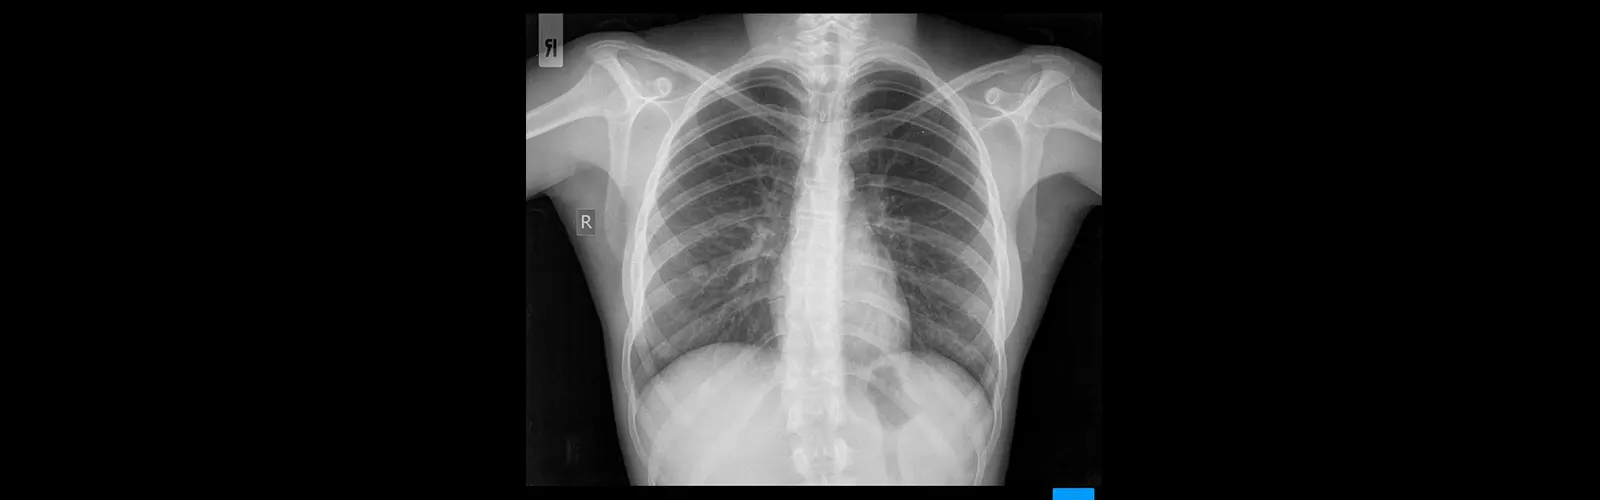

3D imaging gives a more comprehensive see of the chest region than conventional 2D imaging, permitting for more exact visualization of the organs and tissues within the chest.

The utilize of 3D imaging permits physicians to recognize unobtrusive changes within the chest which will be Angiography missed in conventional 2D imaging. This leads to more precise conclusion and treatment arranging.

3D imaging empowers doctors to way better visualize the chest zone and its structures, making a difference to arrange and execute surgical strategies and other medications with more prominent exactness.

3D imaging can help doctors pick up distant better; a much better; a higher; a stronger; an improved a distant better understanding of the life systems of the chest zone, counting the complex connections x-ray between the organs and tissues, chest x-ray which can make strides their capacity to analyze and treat a wide extend of conditions.

CT chest 3D imaging allows for a comprehensive evaluation of the chest area. It provides detailed and highly CECT Whole Abdomen accurate 3D representations of the chest, enabling a more thorough assessment compared to traditional 2D imaging.

CT chest 3D imaging helps in understanding the precise location, size and extent of any abnormality in the chest.